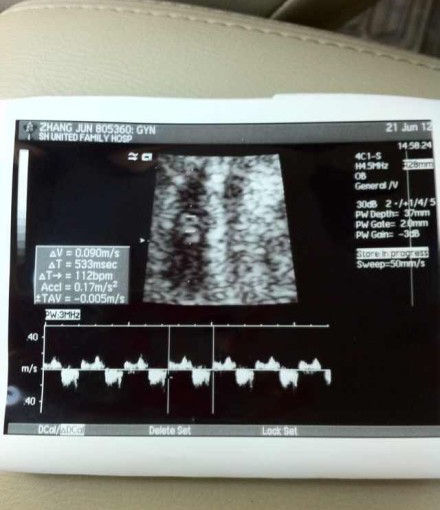

6、回答问题分析 一般情况下做B超是对胎儿不会有太大的影响,但也不易过多,不过由于你目前的情况还不明朗所以还是要听从医生的建议做B超检查 意见建议 大概上胚胎发育,3040天形成的是胎囊,4050天形成的是胎芽,5060天 形成胎心,一般的做B超应该是在60天左右的时候做,这时就能够看到胎囊胎。

7、您好B超是一种无创的检查,一般来说,对胎儿没有影响孕期一般建议做3~5次B超妊娠分为早期中期和晚期,早期的时候应该做一次B超,主要是了解一下您的平均月份和胎儿的大小是否相符合,在中期的时候,一般在2426周的时候,建议做彩超,排除胎儿有没有畸形,排除胎儿畸形的时间,一般是选择在24。

8、如果妊娠期间一切正常的话整个孕期做3次B超检查就可以了第一次B超最好在妊娠1820周做,这一期间,胎儿的各个脏器已发育完全,仔细的B超检查,可看到每一个重要的脏器有无异常可以早期发现胎儿畸形,及时中止妊娠,对母亲身体的影响也较小以后,如果没有异常情况,第二次B超到30周左右做个更。